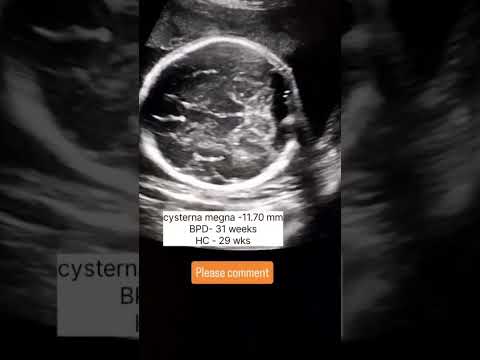

Choroid plexus cyst #choroid #plexus #cyst #ultrasound  — @Fazalhaq Radiology YouTube video